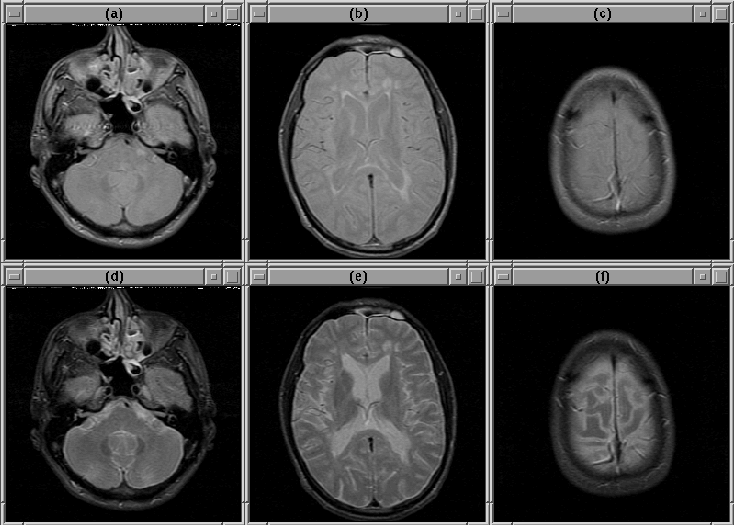

Figure 8.1 shows three slices selected from Data Set 1. The extreme slices (particularly the lowest slice) exhibit considerable partial volume effect resulting in a non-distinct intracranial boundary. The boundary is difficult to detect accurately in these slices. Except for intensity variation due to RF inhomogeneity, other slices in the volume contain no remarkable features.

Figure 8.1: Selected slices from MRI Data Set 1. (Top) PD-weighted. (Bottom) T2-weighted. (a), (d) Slice 1. (b), (e) Slice 14. (c), (f) Slice 27.